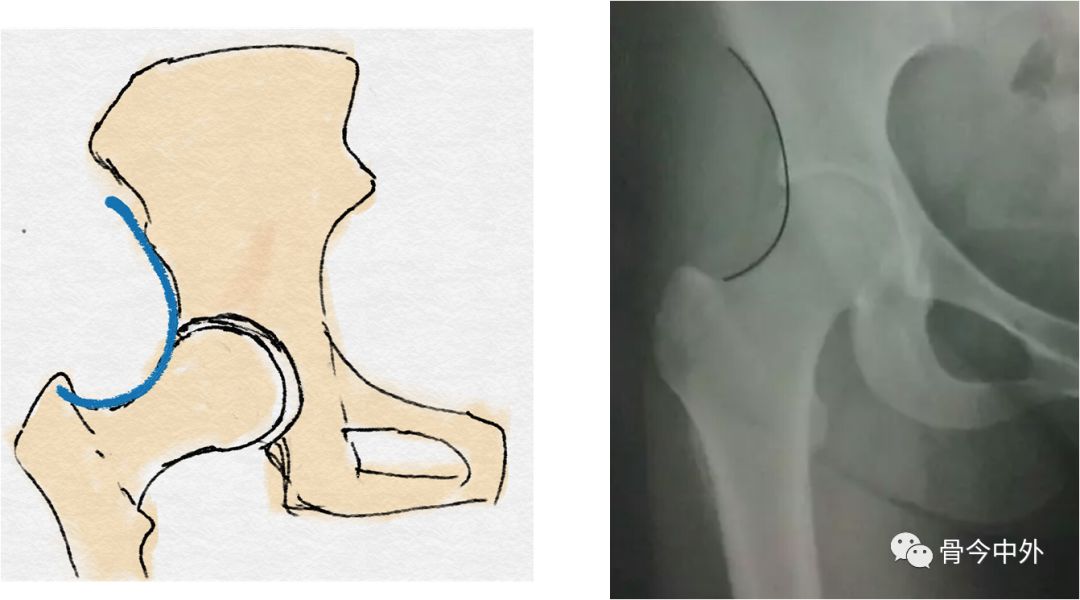

闭孔上缘与股骨颈内下缘连线(正常:平滑曲线)

Shenton线:又叫做兴登线、沈通氏线,是指成人髋关节正位片上,闭孔上缘与股骨颈内下缘连线,正常应为平滑曲线,若不连续提示髋关节脱位或者股骨颈错位骨折。